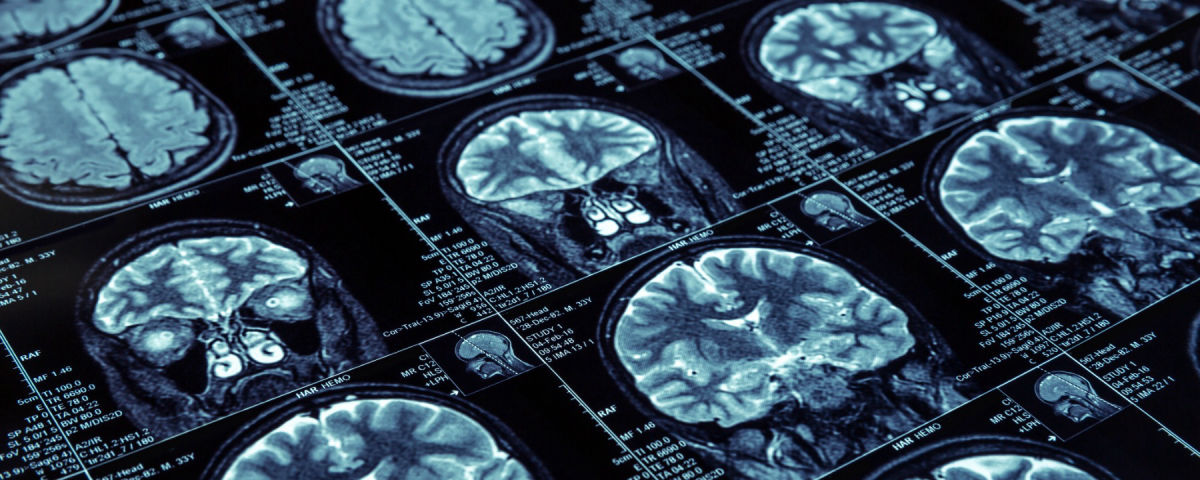

Medical Imaging is the technique and process used to create images of the human body (or parts and function thereof) for clinical purposes (medical procedures seeking to reveal, diagnose or examine disease) or medical science (including the study of normal anatomy and physiology). It is one of the best courses in medical field for students who want to make their career in the national and international healthcare industry.